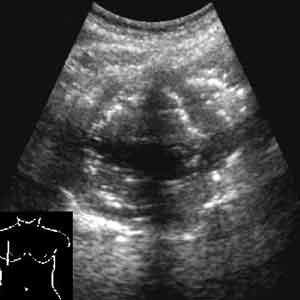

Рис. 7.

Абсцесс легкого.

Новости лучевой диагностики 2002 1-2: 56-60